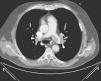

Case 3A 47-year-old woman, obese and with peripheral venous insufficiency, was admitted to the emergency room with syncope, sudden-onset dyspnea, epigastric pain, severe respiratory failure and shock. She had begun taking oral contraceptives three days previously. A few minutes after admission she suffered CPA with pulseless electrical activity and ALS was begun. Spontaneous return of circulation occurred several times but was immediately followed by CPA. TTE showed dilatation of the right chambers (Figure 3A), grade III/IV tricuspid regurgitation (pulmonary artery systolic pressure 45 mmHg above central venous pressure), pulmonary flow suggestive of PH and impaired RV systolic function.

Given the suspicion of obstructive shock due to high-risk PE, intravenous thrombolysis was performed with a 50-mg bolus of alteplase, which resulted in spontaneous permanent return of circulation after around 45 min of ALS. Thoracic CT angiography showed thromboembolic foci in the distal portion of both pulmonary arteries, in the origin of several lobar arteries, and most noticeably in the segmental branches of the right lower lobe artery (Figure 2). As the setting of shock remained refractory to supportive measures, it was decided to perform RT using the AngioJet® system, which resulted in immediate hemodynamic improvement and partial angiographic improvement. The patient remained under ventilatory and inotropic support for 10 days, followed by a favorable clinical course and complete neurological recovery. TTE performed one month after the acute event showed no RV dilatation or dysfunction or signs of PH (Figure 3B). The patient was discharged after 37 days.